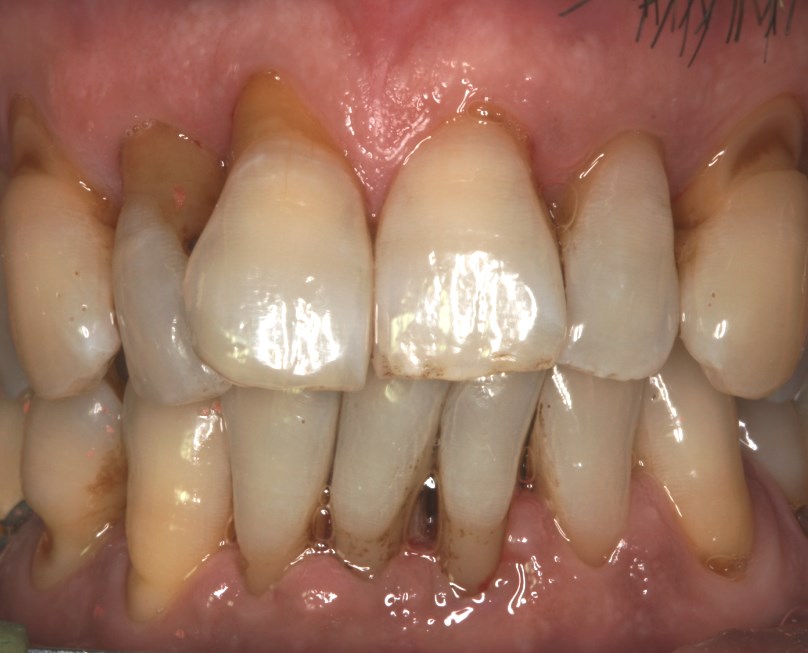

• Περιοδοντίτιδα. Η απώλεια του στηρικτικού οστού του δοντιού συνοδεύεται και από αντίστοιχη απώλεια ούλων και την εικόνα μεγάλων δοντιών. Απαιτείται οπωσδήποτε θεραπεία της περιοδοντίτιδας για να προληφθεί περαιτέρω απώλεια των στηρικτικών ιστών του δοντιού.

Υποχώρηση ούλου από περιοδοντίτιδα

Υποχώρηση ούλου που οφείλεται σε περιοδοντίτιδα